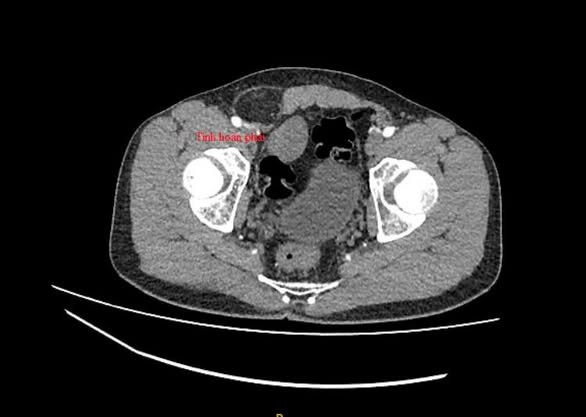

Tại Bệnh viện Xuyên Á, các bác sĩ Khoa Cấp Cứu đã phối hợp với Khoa Ngoại Tổng Quát, Ngoại Tiết Niệu nhanh chóng thăm khám và chỉ định chụp CT 160 cản quang, kết quả phát hiện khối thoát vị bẹn nghẹt và tìm thấy tinh hoàn bên phải trong ổ bụng nằm cạnh bàng quang.

| Tinh hoàn ẩn trên phim chụp - Ảnh BVCC |